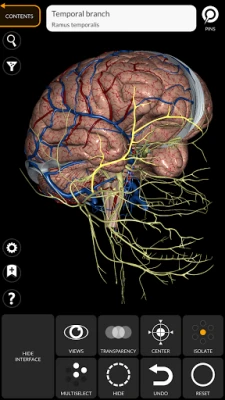

• Nervous system

• Simple and intuitive interface

• Rotate and zoom each model in 3D space

• Option to hide or isolate single or multiple selected models

• Filter to hide or display each system

• Search function to easily find every anatomical part

• Bookmark function to save custom views

• Smart rotation which moves the center of rotation automatically

• Transparency function

• By selecting a model or a pin, the related anatomical term shows up

• Show/Hide UI interface (very useful with small screens)

• The anatomical terms and the user interface are available in 11 languages: Latin, English, French, German, Italian, Portuguese, Turkish, Russian, Spanish, Chinese, Japanese and Korean

• The anatomical terms can be displayed in two languages simultaneously